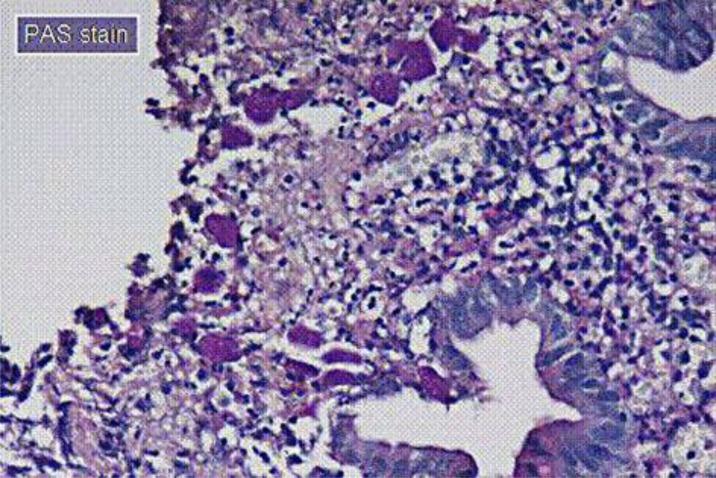

Ameboma is a rare complication of amebic colitis presenting as a mass of granulation tissue with peripheral fibrosis and a core of inflammation related to amebic chronic infection. The initial presentations are usually obstruction and low gastrointestinal bleeding. The most common sites are the ascending colon and the cecum. It may mimic colon carcinoma, Crohn's disease, carcinoma of the colon, non-Hodgkin's lymphoma, tuberculosis, fungal infection, AIDS-associated lymphoma and Kaposi's sarcoma in colonoscopy findings. The therapeutic strategy should be combined with antibiotics for invasive dysentery and eradication of luminal cysts.